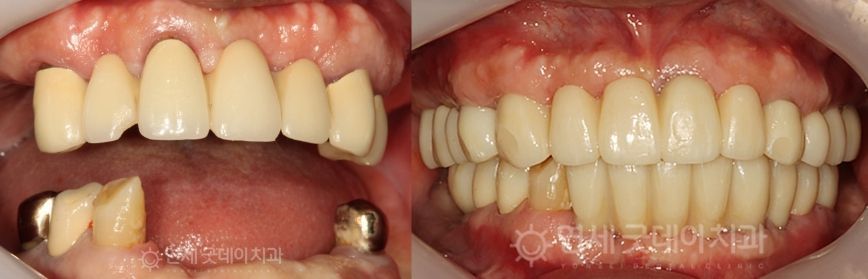

Case Review

Full Mouth Implant Before & After